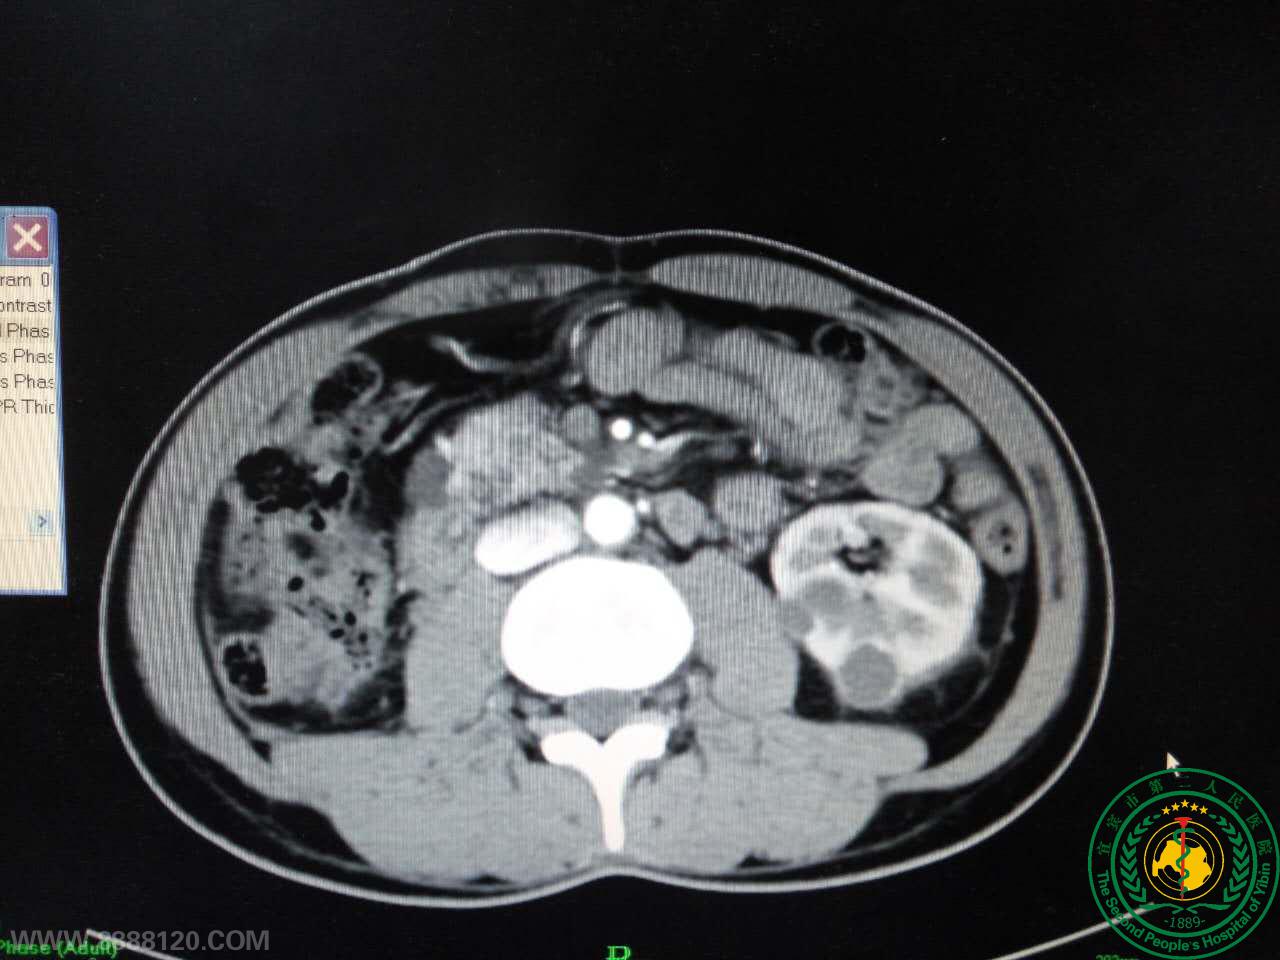

患者CT提示肾多发肿瘤